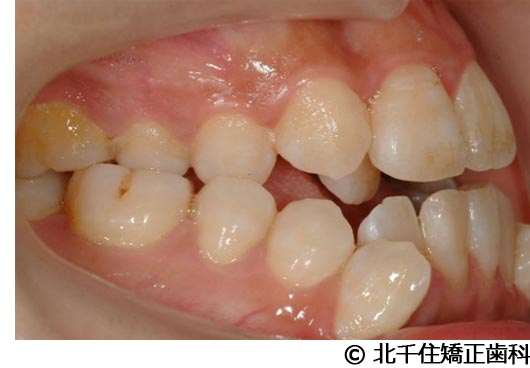

【症例2】上顎前突症

- 治療名

- 上顎前突症

- 年齢・性別

- 19歳10ヵ月・男性(初診時)

主訴:出っ歯、口元の突出、横顔をきれいにしたい

骨格性の上顎前突、上下顎第一小臼歯4本及び上顎第二大臼歯を抜歯して矯正用アンカースクリューを併用してワイヤー矯正治療(セラミックブラケット)。

骨格性上顎前突に対し、抜歯および矯正用アンカースクリューを併用した矯正治療により歯列および咬合関係の調整を行った症例である。治療後は保定装置を使用し、歯列および咬合の安定維持を目的として定期的な経過観察を行っている。